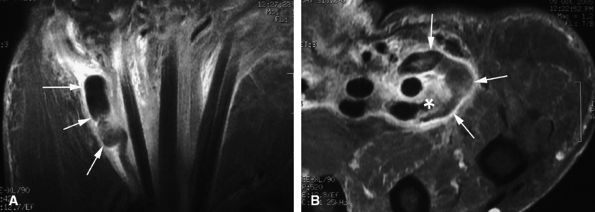

seen with synovial sarcomas. Bone and joint invasion is possible.168 Ultrasonography shows a nonspecific solid mass with a variable color Doppler signal. MR images are specific, depicting a well-defined mass with hemosiderin deposits. Typical signal void artifacts are seen on all sequences, particularly on gradient-echo images, and a more heterogeneous and predominantly low signal is found on T2-weighted images.162,166,169 The lesion typically enhances after intravenous injection of gadolinium (Fig. 11.74). The tendon sheath of the flexor digitorum tendons is usually partially or totally enveloped; the extensor tendons are less commonly involved. Some lesions may be more aggressive, and diffuse lesions are seen in multiple locations with invasion of both the flexor and extensor tendons (Fig. 11.75).170

FIGURE 11.74 ● Giant cell tumor of the tendon sheath. Sagittal T2-weighted image (A) and post-contrast T1-weighted image (B) show a palmar mass (arrows) close to the sheath of the flexor tendons with predominant low signal (arrowhead) on the T2-weighted image and strong enhancement following contrast administration.

FIGURE 11.75 ● Aggressive giant cell tumor of the tendon sheath. Sagittal post-contrast 3D gradient-echo (A) and axial T1-weighted (B) images depicting a multinodular tumor invading the flexor and extensor tendons as well as the head of the phalanx (arrow).